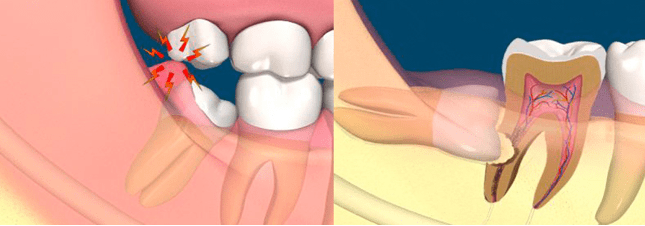

Las extracciones es uno de los procedimientos más agresivos ya que consiste en quitar una o varias piezas de la boca. Una extracción se debería realizar solo en casos en los cuales otros tratamientos para salvar la pieza se hayan evaluado y considerado no adecuados. Las causas más comunes para la extracción dentaria simple son la caries dental y la enfermedad periodontal, asociadas o no a dolor e infecciones repetitivas. Otras causas posibles son: dientes supernumerarios, dientes en áreas sometidas a irradiación, causas protésicas y ortodóncicas.

En La Clínica Dental El Bosque recomendamos la extracción de cordales cuando éstos dañan o afectan a los otros dientes o bien causando caries o al desarrollarse, ya sea porque los empujan o porque salen torcidas o parcialmente. En el caso de que se encuentren incluidas (es decir, que se sitúen bajo la encía y no salgan), también se aconseja su extracción, dado que pueden causar no solo problemas como apiñamiento dental, sino quistes o infecciones.

Hay dos tipos de extracciones; simples y de cordales.